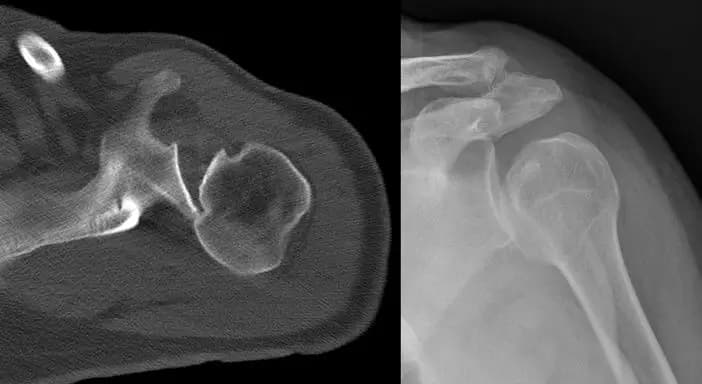

Hill Sachs lezyonu, kol kemiği (humerus) başının posterolateral kısmında kortikal çöküntü oluşması ile karakterize bir omuz yaralanmasıdır. Bu durum, genellikle anterior omuz çıkıkları sırasında meydana gelir. Özellikle humerus başı, glenoidin anteroinferior kenarına şiddetli bir şekilde çarptığında, kemikte kalıcı çöküntü oluşur.

Bu lezyon genellikle omuzun içe dönme hareketi sırasında daha belirgin hale gelir ve doğru şekilde teşhis edilmesi önemlidir. Bilgisayarlı tomografi (BT) veya MR görüntüleme ile kolun hareketi sırasında eklem yüzeyleri detaylı şekilde incelenebilir.